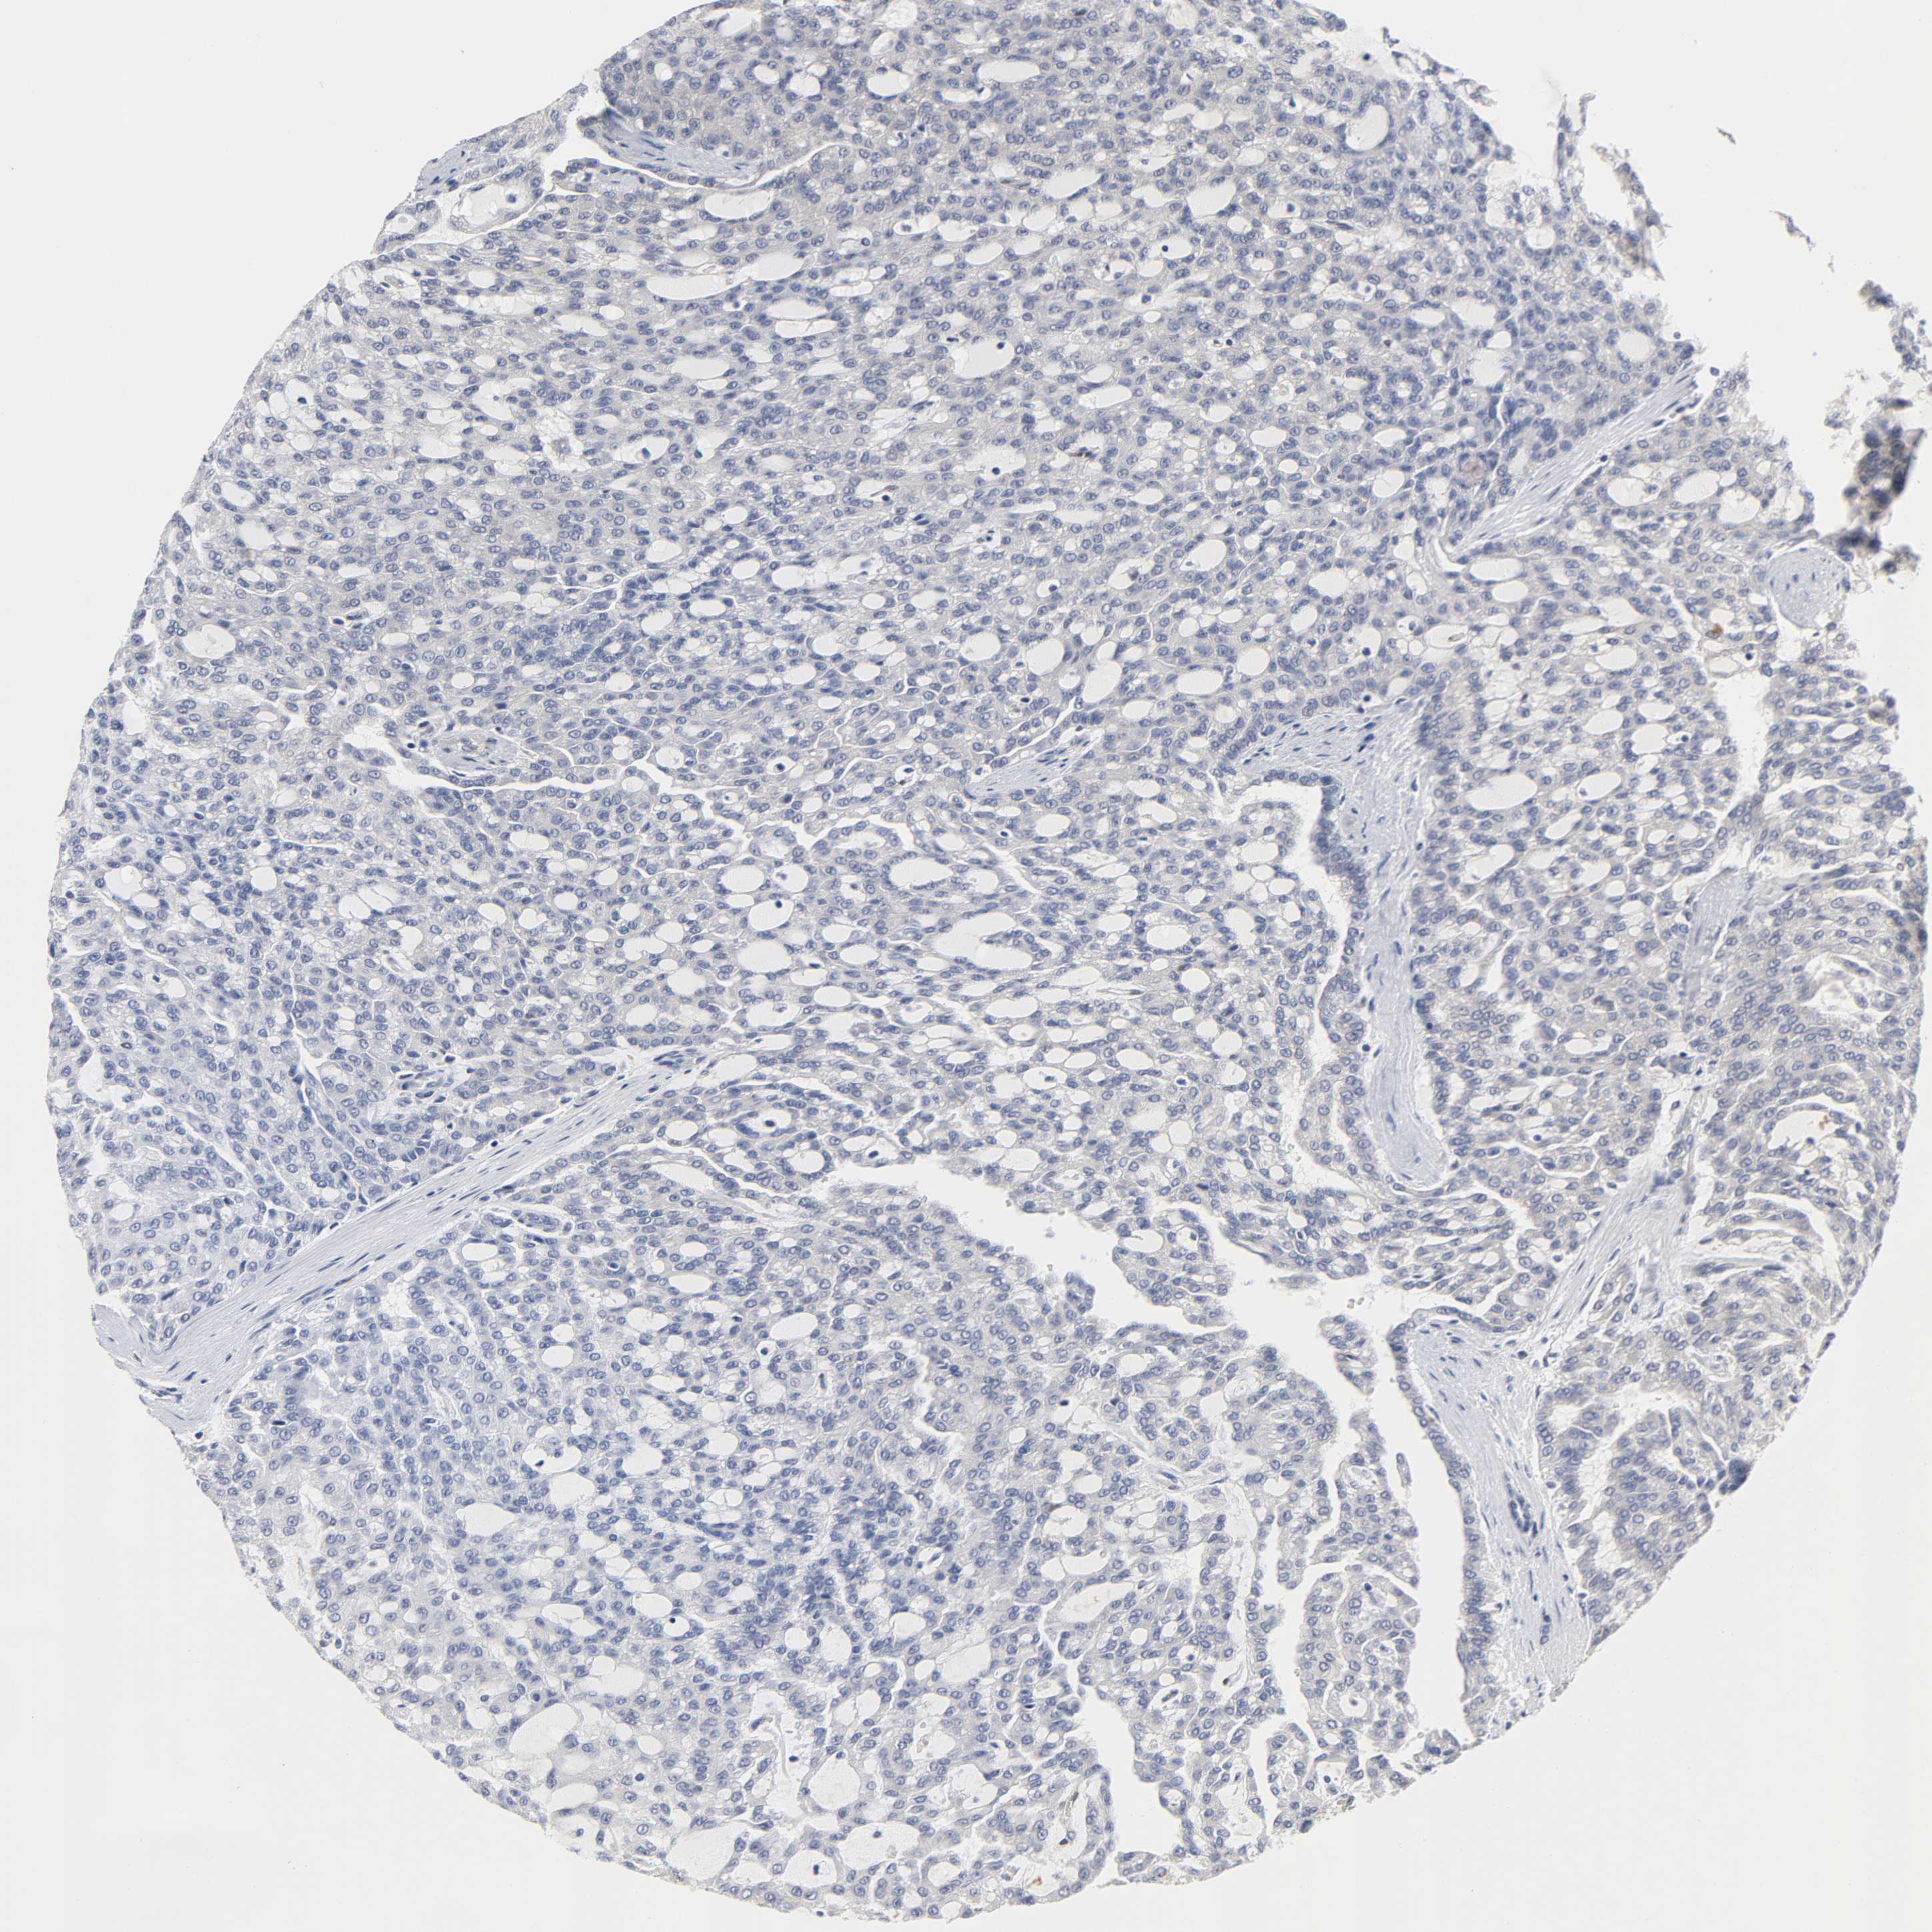

KIDNEY RENAL PAPILLARY CELL CARCINOMA (TCGA) - Interactive survival scatter ploti

The Survival Scatter plot shows the clinical status (i.e. dead or alive) for all individuals in the patient cohort, based on the same data that underlies the corresponding Kaplan-Meier plots. Patients that are alive at last time for follow-up are shown in blue and patients who have died during the study are shown in red.

The x-axis shows the expression levels (FPKM) of the investigated gene in the tumor tissue at the time of diagnosis. The y-axis shows the follow-up time after diagnosis (years). Both axes are complimented with kernel density curves demonstrating the data density over the axes. The top density plot shows the expression levels (FPKM) distribution among dead (red) and alive patients (blue). The right density plot shows the data density of the survived years of dead patients with high and low expression levels respectively, stratified using the cutoff indicated by the vertical dashed line through the Survival Scatter plot. This cutoff is automatically defined based on the FPKM cutoff that minimizes the p-score. The cutoff can be changed by dragging the vertical line or by entering a cutoff value in the square labeled "Current cut-off".

Under the Survival Scatter plot the p-score landscape (black curve; left axis) is shown together with dead median separation (red curve; right axis). Dead median separation is the difference in median mRNA expression between patients who have died with high and low expression, respectively. It is calculated as follows: median FPKM expression of dead patients with high expression - median FPKM expression of dead patients with low expression. This is intended to aid the user in visually exploring custom cutoffs and the associated p-scores and dead median separation.

Individual patient data is displayed and can be filtered by clicking on one or more of the category buttons on the top of the page. Categories describing expression level and patient information include: high, low, alive, dead, female, male and tumor stages. The scale of the x-axis can be toggled between linear and log-scale by clicking on the "x log" button. Mouse-over function shows TCGA ID, patient information and mRNA expression (FPKM) for each patient.

& Survival analysisi

Kaplan-Meier plots summarize results from analysis of correlation between mRNA expression level and patient survival. Patients were divided based on level of expression into one of the two groups "low" (under cut off) or "high" (over cut off). X-axis shows time for survival (years) and y-axis shows the probability of survival, where 1.0 corresponds to 100 percent.

PTEN is not prognostic in Kidney Renal Papillary Cell Carcinoma (TCGA)